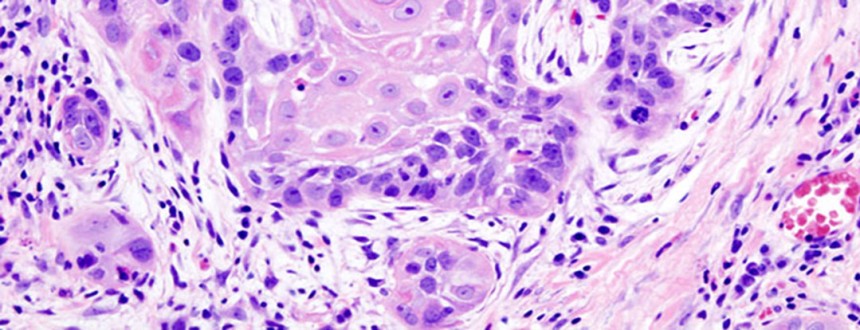

Рак начинается, когда здоровые клетки изменяются и начинают неконтролируемо расти, образуя массу, называемую опухолью. Опухоль может быть раковой и доброкачественной. Раковая опухоль является злокачественной, то есть, может прорастать и распространяться на другие части тела. Доброкачественная опухоль может расти, но не распространяться на другие ткани.

Цель хирургического вмешательства заключается в удалении раковой опухоли и части здоровых тканей во время операции. При раке головы и шеи используются следующие операции:

- Лазерные операции.Этот способ может использоваться для лечения опухоли на ранней стадии, особенно если она была обнаружена в гортани. Удаление. Это операция по удалению раковой опухоли и части окружающих ее здоровых тканей, известных как край.

- Лимфодиссекция, или шейная диссекция.Если врач подозревает распространение раковой опухоли, он может удалить лимфатические узлы на шее. Это может быть сделано одновременно с проведением удаления опухоли.

- Реконструктивная (пластическая) хирургия.Если для хирургического лечения рака требуется удаление важного участка ткани, например, удаление челюсти, кожи, глотки или языка, может потребоваться реконструктивная или пластическая операция для замены отсутствующей ткани. Эта операция помогает восстановить внешний вид человека и функциональность отдельных органов. Логопед потребоваться, чтобы заново научить больного глотать и общаться, используя новейшие методики.

Исходя из расположения, размеров, вида рака, процесс лечения будет проходить поэтапно с проведением нескольких операций.. При невозможности полного устранения опухоли рекомендуются дополнительные процедуры. Если раковые клетки остаются после оперативного вмешательства, назначают другие виды онкологической помощи (радио-, химиотерапия) в сочетанном или изолированном виде.